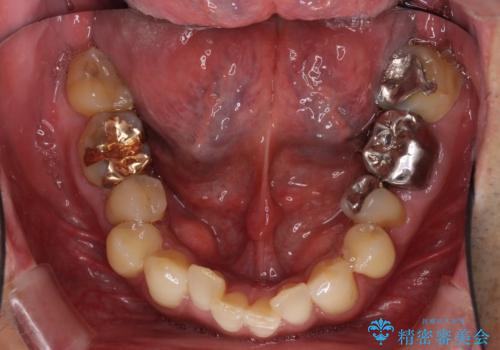

歯列不正と歯周病 総合歯科治療による全顎治療

- 前歯がのデコボコや、奥歯に咬んだときに痛みがあるとのことで来院された患者様です。

全体的に問題が多く、全てをしっかりと治療したいとのことでした。

全体的に中等度の歯周病と診断されたため、歯周外科処置やインプラントによる咬合回復から進めて行き、矯正治療による歯列改善を行った後にオールセラミッククラウンにて補綴することとしました。

歯槽骨の再生治療を行ったため、外科処置後の静置期間がながくなり、4年弱の治療期間となりました。